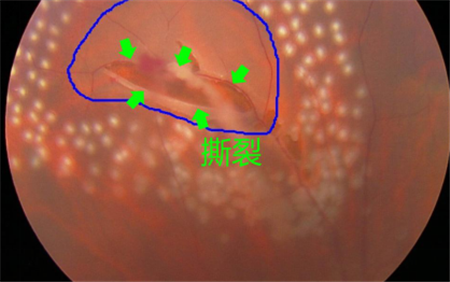

如果是一些嚴(yán)重眼疾如后玻璃體脫落、視網(wǎng)膜撕裂、糖尿眼或老年黃斑退化導(dǎo)致玻璃體出血、葡萄膜炎等導(dǎo)致的飛蚊癥,則屬于病理性飛蚊,也稱為惡性飛蚊。這些眼疾若未及時(shí)治療,嚴(yán)重情況下可導(dǎo)致眼睛失明。

例如,對(duì)于視網(wǎng)膜撕裂引起的飛蚊癥,就需要對(duì)視網(wǎng)膜撕裂進(jìn)行治療,通過(guò)激光將裂孔周?chē)M(jìn)行燒焊凝固,以避免積水?dāng)U散造成嚴(yán)重的視網(wǎng)膜脫落;若飛蚊癥是由葡萄膜炎所致,就需要及時(shí)治療葡萄膜炎;對(duì)于糖尿眼導(dǎo)致的玻璃體出血,則需要通過(guò)激光治療以減少或避免增生血管的產(chǎn)生。